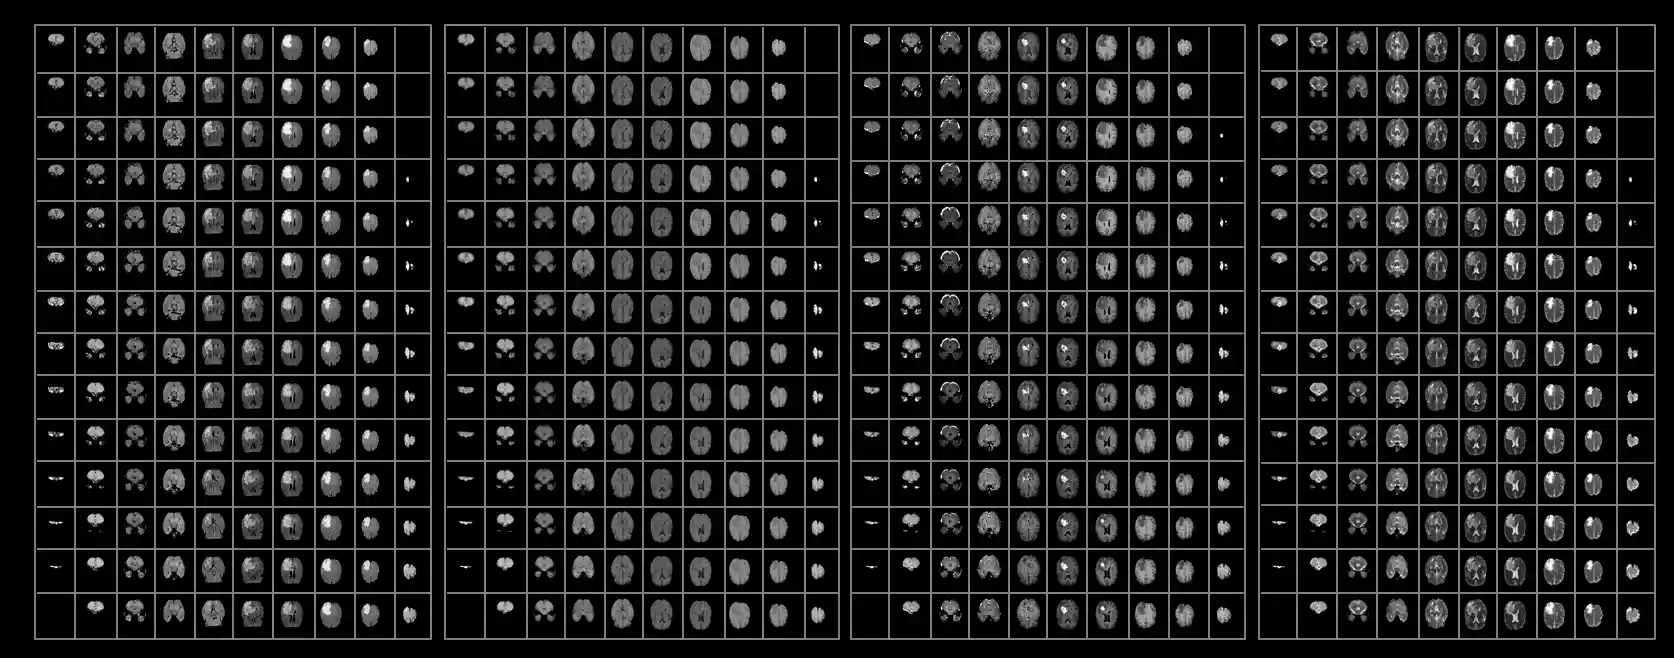

Notice now that a single patient will produce upwards of 600 images from a single MRI, given that all four sequences produce 155 slices each (Figure 5). To get a satisfactory manual segmentation a radiologist must spend several hours tediously determining which voxels belong to which class. In the setting of malignant brain tumors, an algorithmic alternative would give clinicians more time focusing on the wellbeing of the patient, allowing for more immediate patient care and higher throughput treatment times.

Figure 5: (Top) Representative scans from each tumor imaging sequence. Approximately 600 images need to be analyzed per brain for a segmentation. (Bottom) The results of a complete tumor segmentation.Automatic tumor segmentation has the potential to decrease lag time between diagnostic tests and treatment by providing an efficient and standardized report of tumor location in a fraction of the time it would take a radiologist to do so.